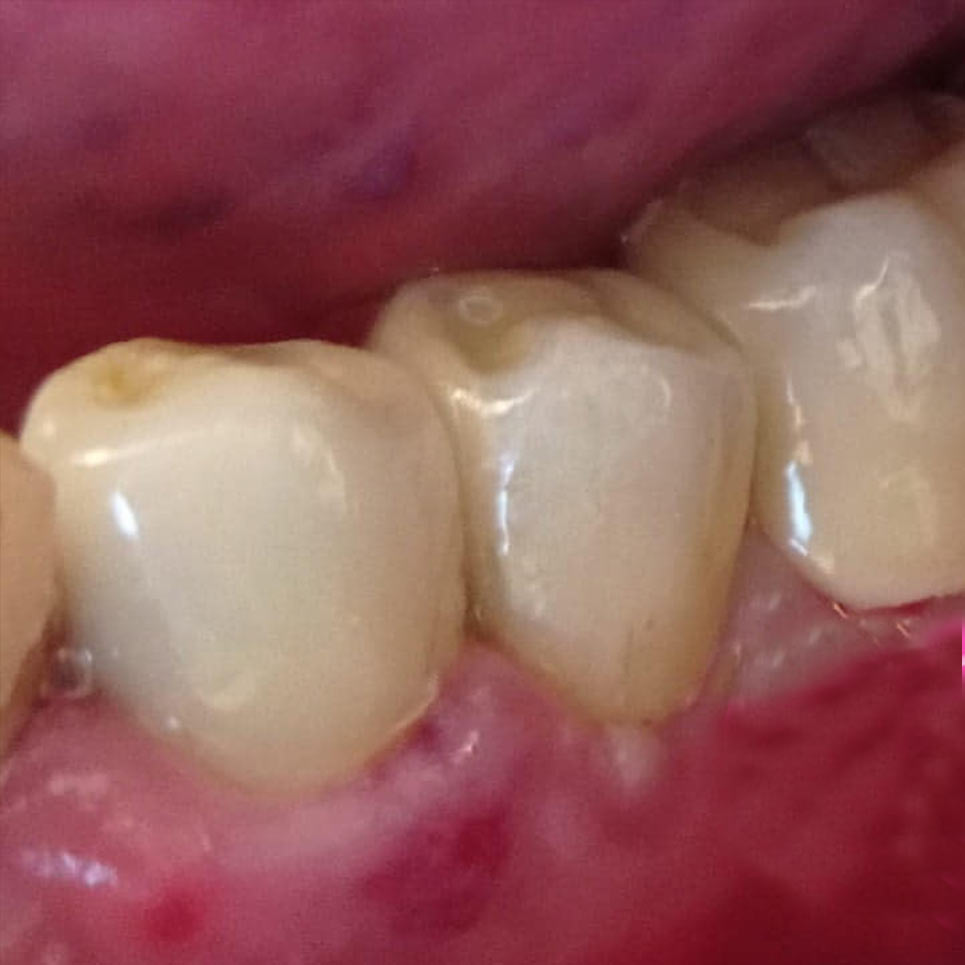

Την ίδια ημέρα που παρασκευάζουμε ~ κατά κόσμον τροχίζουμε ~ τα δόντια, φεύγετε την ίδια ημέρα, ναι καλά διαβάζετε με δόντια , ‘’ προσωρινά ‘’ ~ μεταβατικές αποκαταστάσεις ~, χωρίς καμία επιπλέον χρέωση, και έτσι διατηρούμε το χαμόγελο σας, αισθητική και ανάγκες καθημερινές μέχρι να ‘’ βάλουμε ‘’ τα τελικά μας δόντια!

Με σωστή τήρηση και ευλάβεια και σεβασμό στη βιολογία, φυσιολογία και ανατομία του στόματος , ιστών , δοντιών, παρασκευάζουμε τα δόντια άρτια, όμορφα και με ευγένεια για αναπληρώσουμε τις όποιες απώλειες δοντιών, καταστροφές, φθορές και φυσικά αισθητικές ανάγκες.